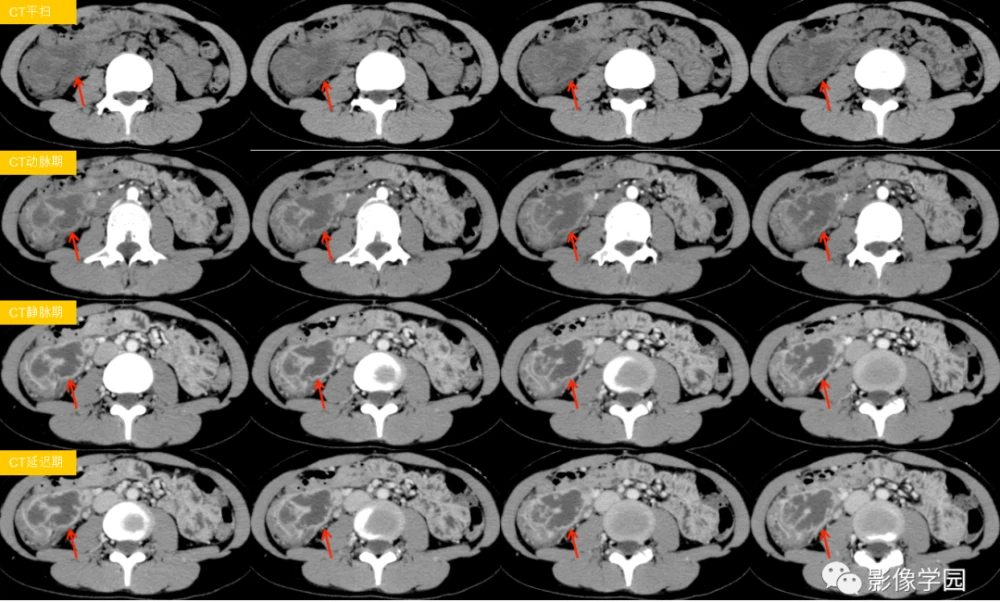

诊断这个病,可不是件容易的事。医生们得通过一系列的检查,比如血液检查、粪便检查、内窥镜检查,甚至是CT或MRI扫描,来确定我身体里这个小恶魔的存在。每项检查都像是在和这个病玩捉迷藏,让人心力交瘁。